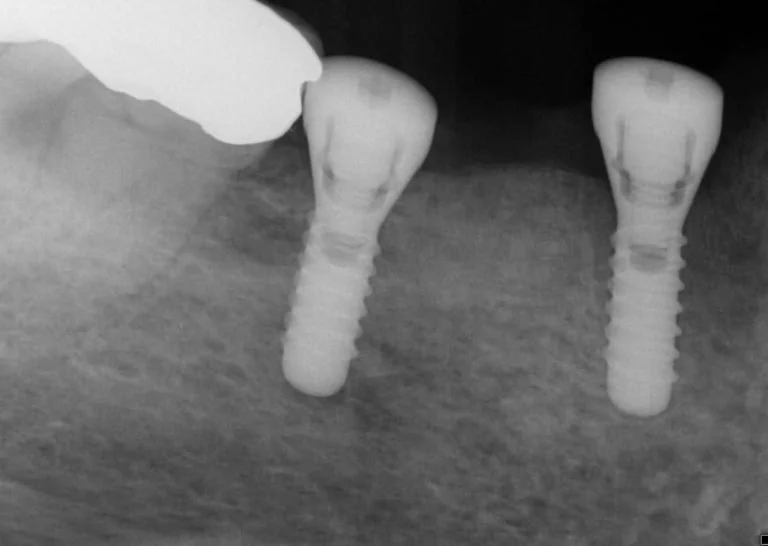

Once healing and adequate bone volume above the mandibular canal had been confirmed, two Bioconcept 3.3mm x 10mm tissue level implants were placed in sites 44 and 46. Several careful progressive intraoperative periapical radiographs were taken to confirm vertical position relative to the mandibular canal. Both implants were then placed with a primary stability of over 30 Ncm as a one stage surgical procedure, and 2mm healing abutments were then secured.

Following three months healing time, osseo-integration was then confirmed with the usual methods, combined with ISQ measurements (Ostell), to confirm readings of over 65 for adequate stability to allow for restoration.

Open tray screw retained impression copings were then attached and confirmed with radiographs, and a three-unit veneered zirconia bridge was constructed using Variobase lab cemented abutments to provide an all-in-one screw-retained restoration.